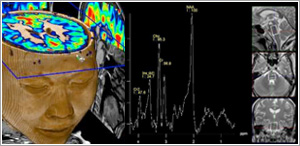

MR Spectroscopy (MRS)

MRS is a relatively new clinical procedure that allows detection of biochemical abnormalities within the brain. It is generally performed in addition to an MRI scan